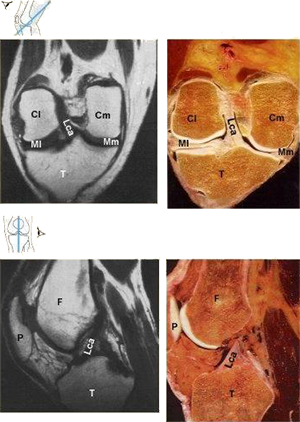

Dieser Bild zeigen Kernspin-Tomographien und anatomische Schnitte des Kniegelenkes.

In der Graphik ist links jeweils das Schnittbild plaziert, rechts ein anatomischer Schnitt. In der Skizze oben ist die Schnittführung angedeutet.

Dieses ist ein Schrägschnitt (vgl. Skizze ganz oben), dem vorderen Kreuzband (Lca) [Ligamentum cruciatum anterius] folgend. Gut sichtbar sind die innere und äußere Kufe des Oberschenkelknochens (Cm) [Condylus medialis femoris], (Cl) [Condylus lateralis femoris] und der Schienbeinkopf (T) [Tibia]. Dazwischen liegen die Menisken (Mm) [Meniscus medialis], (Ml) [Meniscus lateralis].

Hier wurde wiederum etwa entlang dem vorderen Kreuzband (Lca) geschnitten, jedoch in Längsrichtung. Vor dem Oberschenkel (F) [Femur] ist die Kniescheibe (P) [Patella] zu sehen.